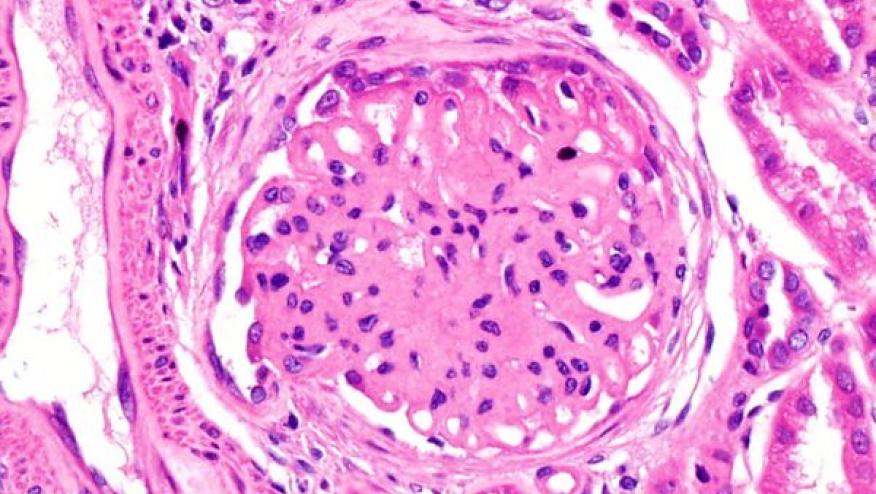

First: kidney biopsy is vital for assessment of suspected LN. Not only for diagnosis but also prognostication and to help tailor therapies. It also has a role to re-assess patients who are refractory to therapies.